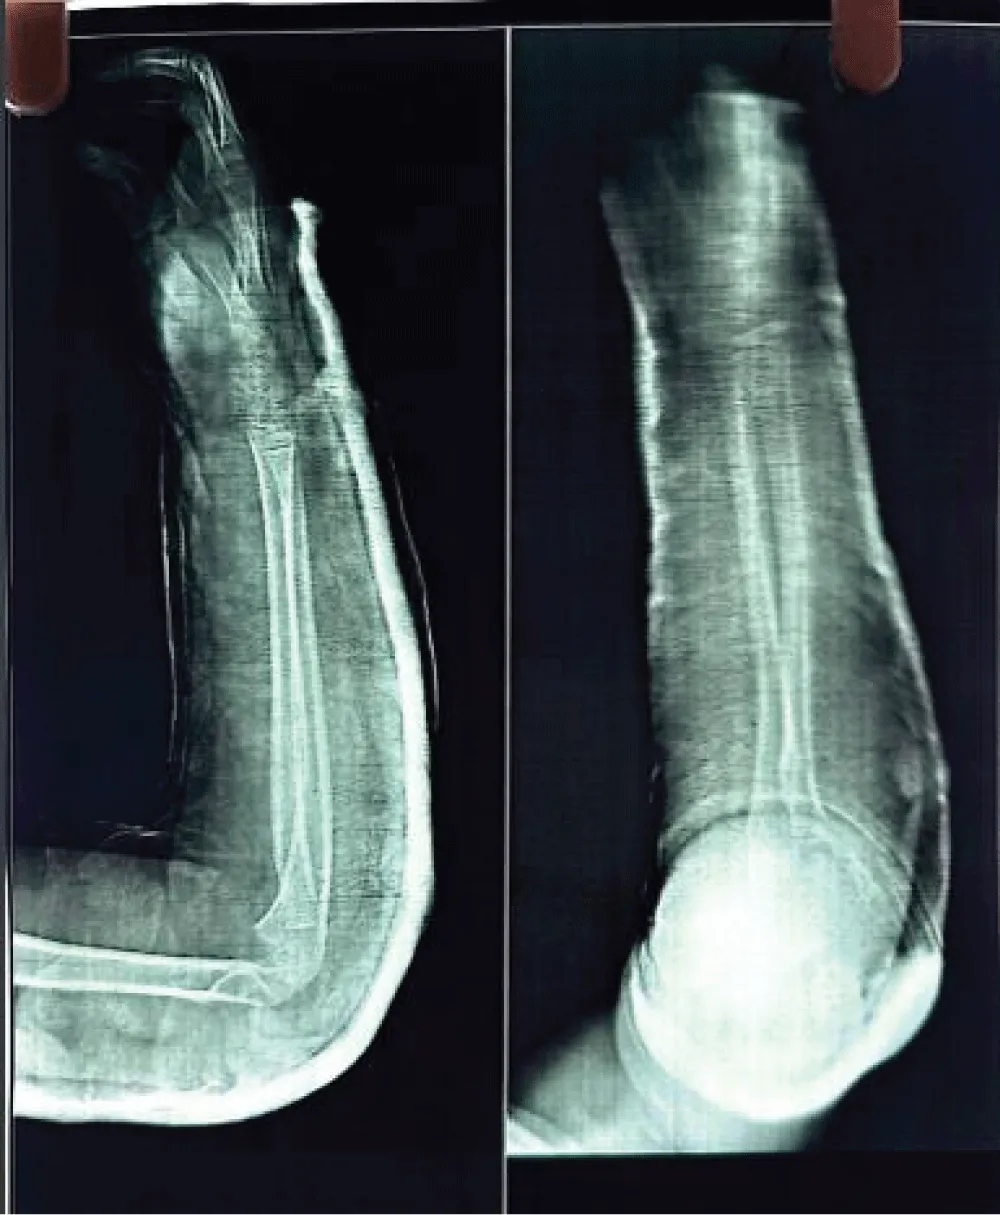

A mother with 6 year old female child presented to our Orthopedic Out Patient Department. She had not been able to move her right elbow in full range with restricted active and passive movements and appeared distressed. According to the informant (mother), she had been apparently well 2 months back when she was hit by rear wheels of a tractor while playing on the roadside. She developed pain and swelling in the elbow and was immediately rushed to the nearby hospital. Routine investigations, CT scan of abdomen and pelvis and X-ray of right elbow and hand were done. (Figures 1-3). All reports were normal except X-ray arm diagnosing undisplaced low lying supracondylar fracture of the right humerus (Figure 3). The child was admitted to the hospital and right upper limb was immobilized in an above-elbow plaster slab, with the elbow in 90o flexion (Figure 4). She was discharged after 4 days with reportedly normal radiographic findings.

Then she was presented to our centre and physical examination revealed a non-discrete soft-tissue mass, approximately 2 × 4 cm in size, that was deep to muscle and tender on palpation (Figure 6). Grip strength in the right hand was normal; right biceps and triceps strength were rated as 3/5. Range of motion at the elbow was limited due to pain, and the patient was unable to lift her left arm over her head.